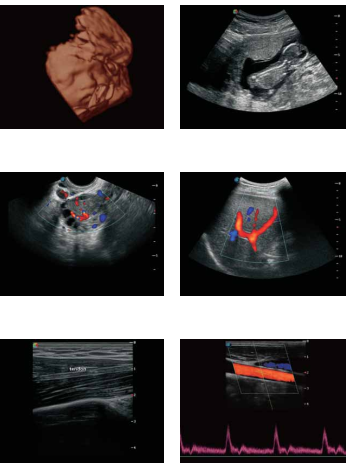

- **2D:** Hình ảnh siêu âm trắng đen cơ bản, được sử dụng phổ biến trong hầu hết các ứng dụng siêu âm.

- **3D/4D:** Cho phép tái tạo hình ảnh không gian ba chiều và bốn chiều của các cấu trúc bên trong cơ thể, hữu ích trong siêu âm thai nhi và các cấu trúc phức tạp.

- **Doppler màu:** Hiển thị dòng chảy của máu trong các mạch máu bằng màu sắc, giúp xác định tốc độ và hướng dòng chảy.

- **Doppler năng lượng:** Đánh giá lưu lượng máu với độ nhạy cao, đặc biệt hữu ích trong việc phát hiện các dòng chảy nhỏ hoặc chảy chậm.

- **Doppler xung:** Cung cấp thông tin chi tiết về tốc độ dòng chảy máu tại một vị trí cụ thể.

- **M-mode:** Ghi lại chuyển động của các cấu trúc bên trong cơ thể theo thời gian, thường được sử dụng trong siêu âm tim.